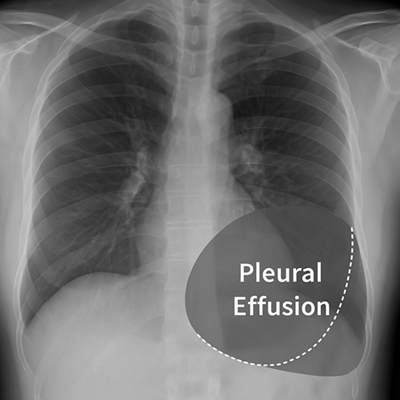

- Radiografía de tórax: detecta derrames >200 ml en proyección posteroanterior.

- Ecografía torácica: más sensible, útil en volúmenes pequeños y para guiar procedimientos.